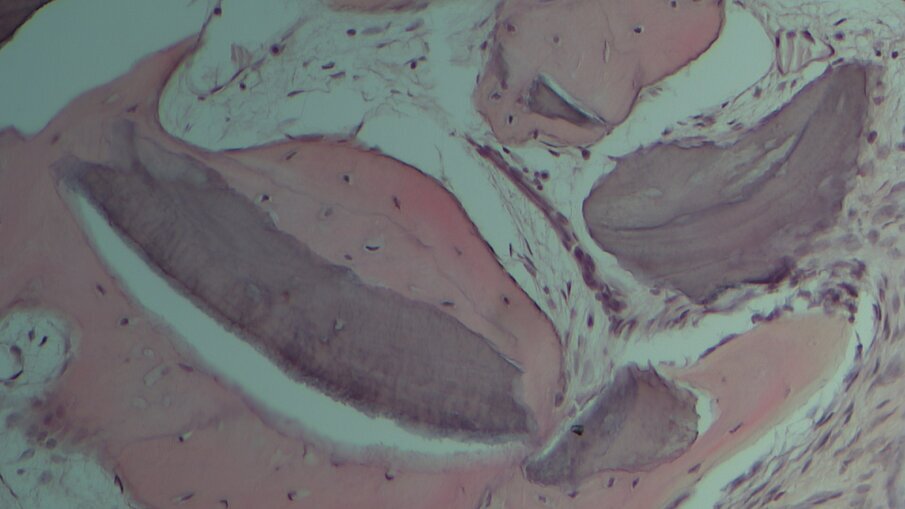

L’esame istologico ha rivelato che il biomateriale era quasi completamente riassorbito. Non erano presenti segni di infezione e la lamina non era staccabile né clinicamente né nelle immagini istologiche. La morfologia ossea mostrava un osso maturo e mineralizzato (Figg. 3, 4). Con riferimento alla larghezza e altezza media della cresta sono stati registrati rispettivamente un guadagno di 2,36 ± 0,69 mm e 3,13 ± 0,90 mm. Non si sono verificate complicanze.